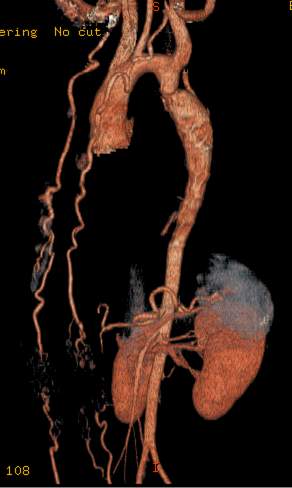

Image

Contrast enhanced MR angiography

Control CT angiography after stent implantation to correct a bilateral arterial stenosis

Fig. 18., 19.: Renal artery stenosis